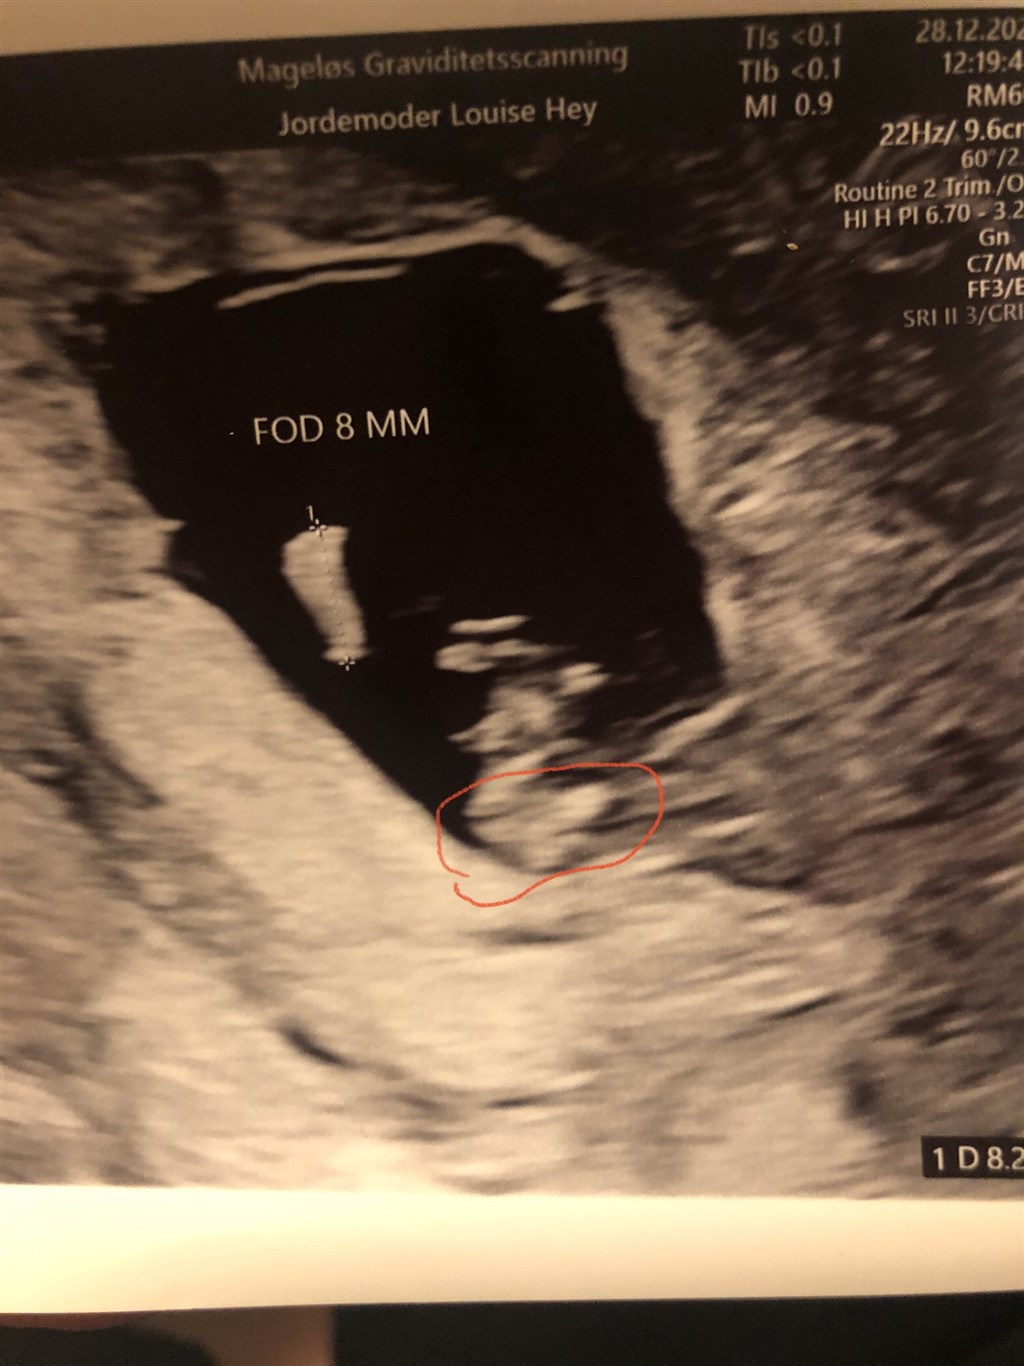

Det er for tidligt at vurdere køn, din babys Nub kan pt gå begge veje, så jeg tør ikke konkludere noget